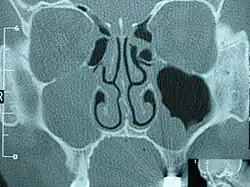

![]() TK śuzowiaka prawej zatoki szczękowej, powodującego wybrzuszenie wyrostka haczykowatego kości sitowej | |

Diagnostyka jedynie radiologiczna. Daje to obraz zakresu ekspansji śluzowiaka, jej położenie, stosunki anatomiczne z innymi strukturami, co jest kluczowe dla zaplanowania leczenia operacyjnego na oddziale otolaryngologicznym. Podstawowym badaniem jest TK zatok przynosowych w kilku projekcjach. Wartość diagnostyczna zwykłego zdjęcia rentgenowskiego zatok przynosowych jest oceniana jako raczej znikoma. Badanie MRI pokazujące bardzo dobrze tkanki miękkie uzupełnia jedynie badanie TK, gdyż nie widać na nim kości, co jest ważne dla określenia np. zniszczenia kości przez śluzowiaka.